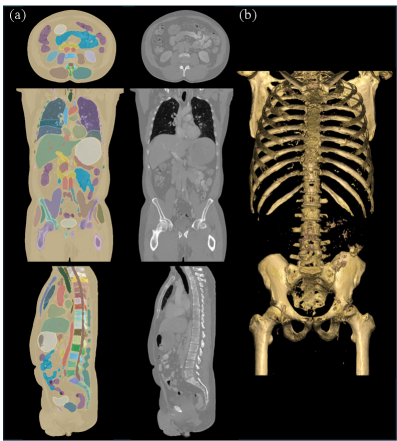

Refer to caption

Figure 1: (a) A generated high-resolution CT volume (with volume dimensions of 512 ×\times 512 ×\times 768 and voxel spacing of 0.86 ×\times 0.86 ×\times 0.92 mm3\text{mm}^{3}) by the proposed method and its corresponding segmentation condition overlaid on generated volume. We show the axial, sagittal, and coronal views from top to bottom, respectively. (b) 3D volume rendering of generated CT by MAISI. The rendering setting is tuned to highlight bone structures and demonstrate the realism of the generated CT volume.